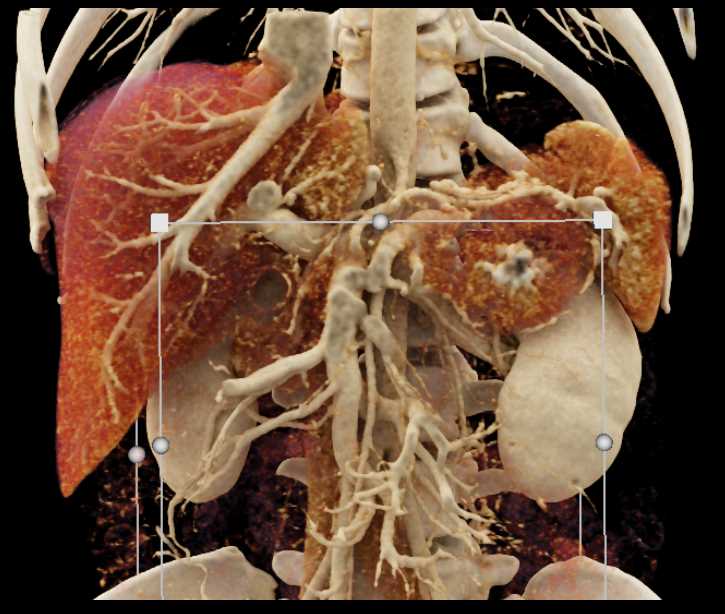

Neuroendocrine Tumor Pancreas